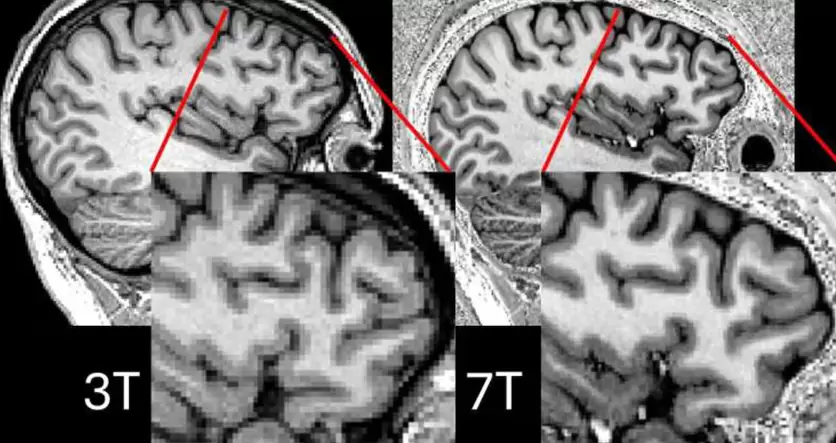

La resonancia magnética de 7T identifica lesiones cerebrales que antes eran indetectables.

Diferencias de 3T y 7T del mismo participante (Créditos:Simon Jones, Universidad de Cambridge).